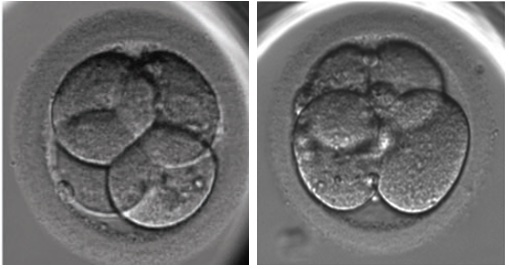

To grade a cleavage stage embryo there’s 3 things you can look at: cell number, fragmentation, and symmetry.

Cell number is considered to be the most important factor in determining the potential for a cleavage stage embryo. Each cell divides at a certain rate to give a total number by a certain day. On day 2 that number is 4 cells and on day 3 it’s 8 cells. Not all embryos will have these numbers on these days, some might go a bit slower (or faster!) and that’s okay. But an embryo with an ideal number typically has the best chance.

Fragmentation is a phenomenon where a cell of a cleavage stage embryo pinches off a tiny piece of a cell called a fragment. It’s not clear what the purpose of this is but may indicate that the cell is dying. Fragmentation is measured by the percentage it occupies in an embryo and less than 10% is considered ideal.

Symmetry is how evenly sized each cell in a cleavage stage embryo is. If all the cells are the same size, this is a good sign! It means that they divided equally and all the “stuff” inside the cells was split up properly. Otherwise, in the case where many of the cells aren’t evenly sized, this is an indication of poor embryo quality. Often high fragmentation and poor symmetry correlate with each other.